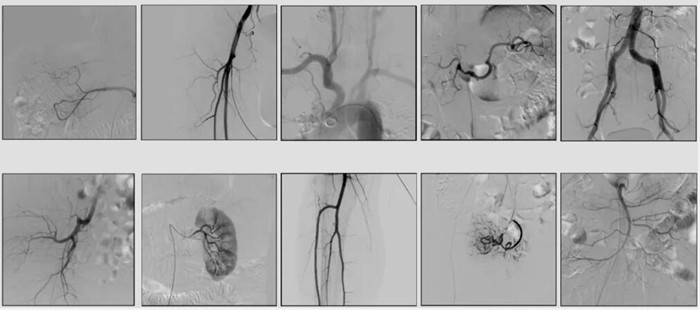

2)中C,学名外周介入C形臂(Peripheral Interventional C-Arm)。与小C相比,中C不仅大幅提高了X射线系统功率,更重要的是增加了减影等血管机相关功能,基本可以完成80%的介入手术需求,主要应用在周围血管科、消化内科、妇科、整形科等领域。

中C在周围血管领域有重要价值